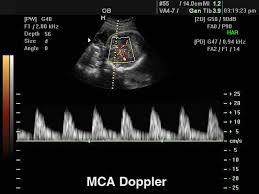

4.Υπερηχογράφημα  ανάπτυξης του εμβρύου  και μελέτη Doppler.  24-42 εβδομάδες

Συνιστάται η παρακολούθηση όλων των εγκύων στις 30-32 εβδομάδες προκειμένου να ελεγχθεί η ενδομήτρια ανάπτυξη και η συμπεριφορά του εμβρύου. Ωστόσο ιδιαίτερα ο έλεγχος αυτός συνιστάται όταν υπάρχουν και επιπλοκές της εγκυμοσύνης ή επιβαρυμένο ατομικό και μαιευτικό ιστορικό. Η εκτίμηση της ενδομήτριας υγείας του εμβρύου γίνεται με:

• Μέτρηση της περιμέτρου της κεφαλής , κοιλιάς και μηριαίου οστού και υπολογισμός του πιθανού βάρους του εμβρύου

• Εξέταση των κινήσεων του εμβρύου

• Εκτίμηση της θέσης και υφής του πλακούντα

• Υπολογισμός της ποσότητας του αμνιακού υγρού

• Έλεγχος της αιματικής ροής προς τον πλακούντα και το έμβρυο με έγχρωμο Doppler.